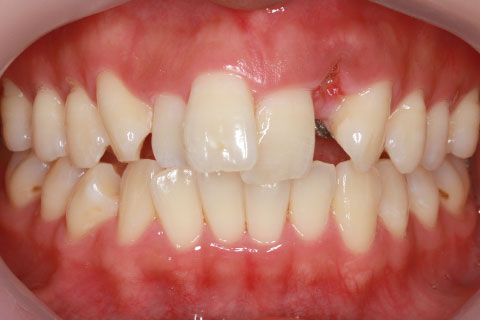

フルリンガル矯正1:上下の歯を舌側矯正で治療(矯正期間24ヶ月)

- 年齢・性別

- 33歳女性

- 治療期間

- 2年0ヶ月

- 抜歯

- 上顎4番抜歯。下顎5番欠損。

- 治療費

- 120万円(税込み)

- フルリンガル矯正

- 治療内容

- 上顎前歯の叢生改善および下顎前歯の空隙閉鎖

- 施術の副作用(リスク)

- 装置が裏側について、目視ができないため、しっかりとブラッシングができているかどうかわかりにくい。